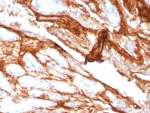

IHC staining of FFPE human prostate carcinoma tissue with Decorin antibody (clone DCN/3521). Inset: PBS used in place of primary Ab (secondary Ab negative control). HIER: boil tissue sections in pH 9 10mM Tris with 1mM EDTA for 20 min and allow to cool before testing.